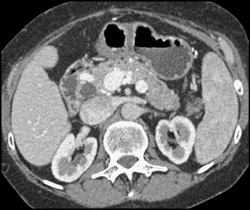

Aortic Dissection With Decreased Left Renal Function